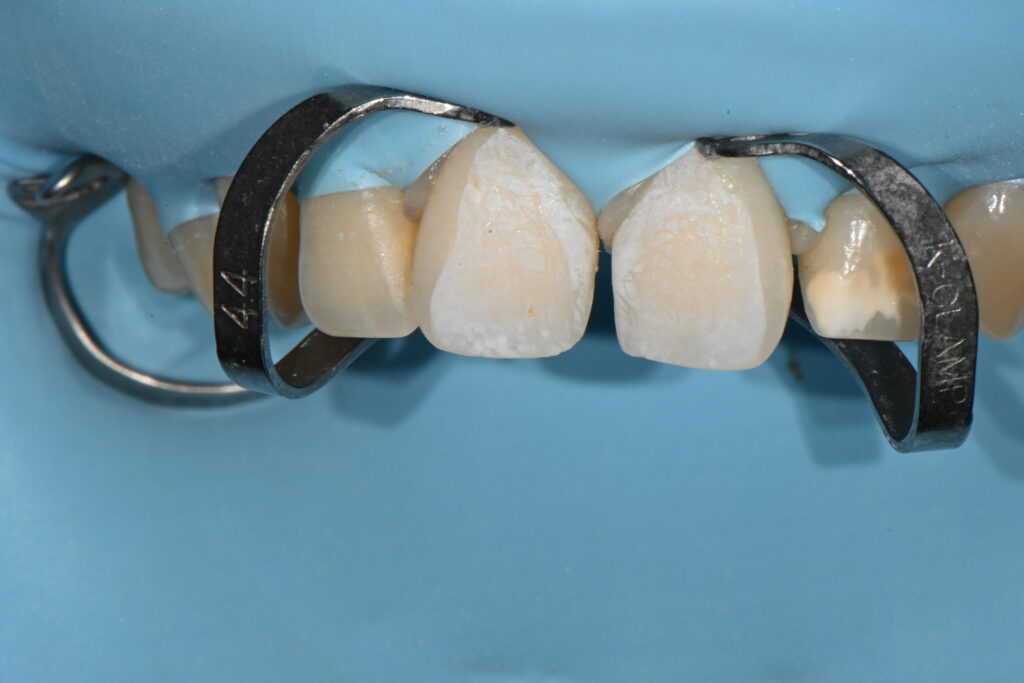

제일 중요한 과정은 러버댐이라는 재료를 결착하여

충분히 방습을 하면서

깨끗하고 이물질이 들어가지 않도록 러버댐을 체결해줍니다

에칭이라는 표면과정이 끝나고 러버댐 체결이 완료된 준비상태

일단 이과정 자체가 매우 어렵고 번잡합니다

하지만 제일 중요한 과정이기도 하지요

특히 앞니 레진의 경우 시간이 1시간이상이 걸리기 때문에

이 과정이 필수이지요

완벽히 격리된 진료환경이 되어야 치료 결과가 좋습니다